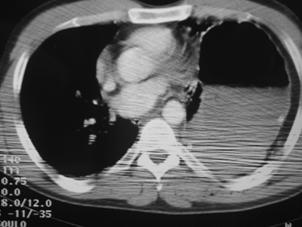

Corp ascutit penetrat in regiunea precordiala Mediastin largit

Aortograma Mediastin largit

Leziune la nivelul istmului aortic

Aortograma.Leziune

situata distal de Aorta

clampata

emergenta arterei subclavii stangi Segment

lezat excizat